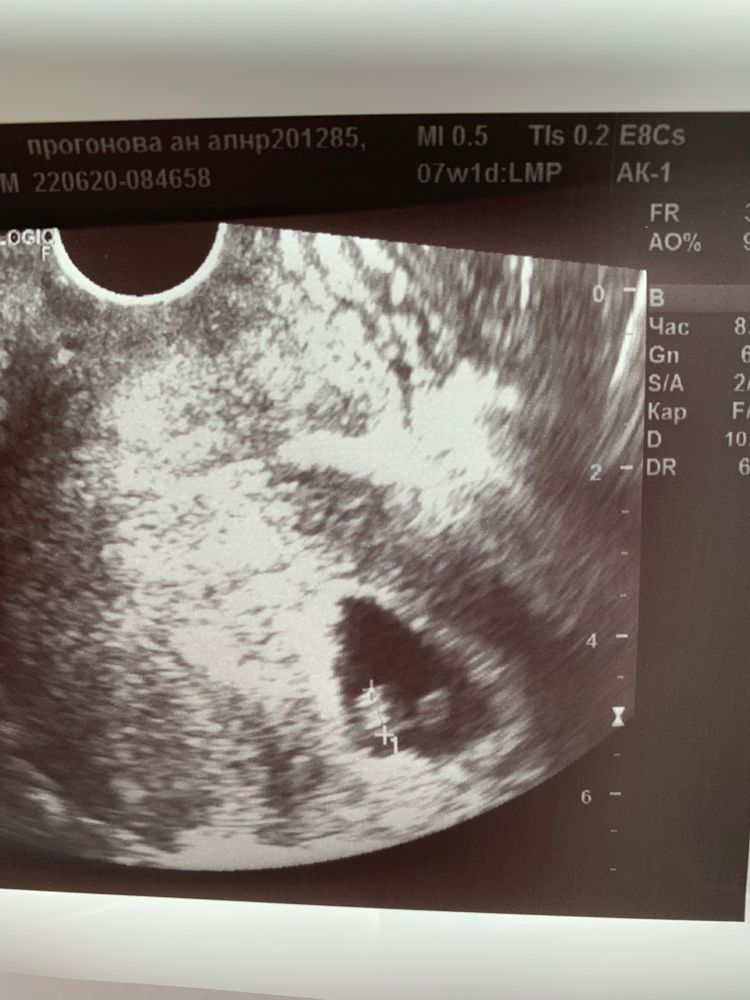

Марина, а у меня вот так.тоже слева и не совпало!)

16.11.2020

Марина, здорово! Метод значит скорее работает, чем нет)